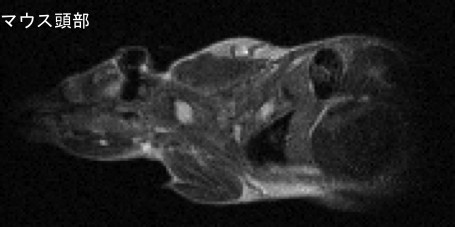

我が国でも最も高齢化が進んだ島根県において、認知症医療は最重要課題の一つであります。そこで今回のコホートを使って、認知症に関する新たな診断・解析方法を開発します。特に検診など多数の対象者に使用可能な、迅速で簡便な認知機能評価装置の開発を予定しています(写真2)。この装置を用いて、栄養やソーシャルキャピタルと認知機能の関連について検討を行います。また、酸化ストレスマーカーなど認知症疾患に関係するバイオマーカーの迅速な測定システムの開発を行います。さらに、認知症の原因物質であるアミロイドの脳内沈着を早期に検出できる造影剤の開発による認知症早期診断技術の開発を目指します(写真3)。